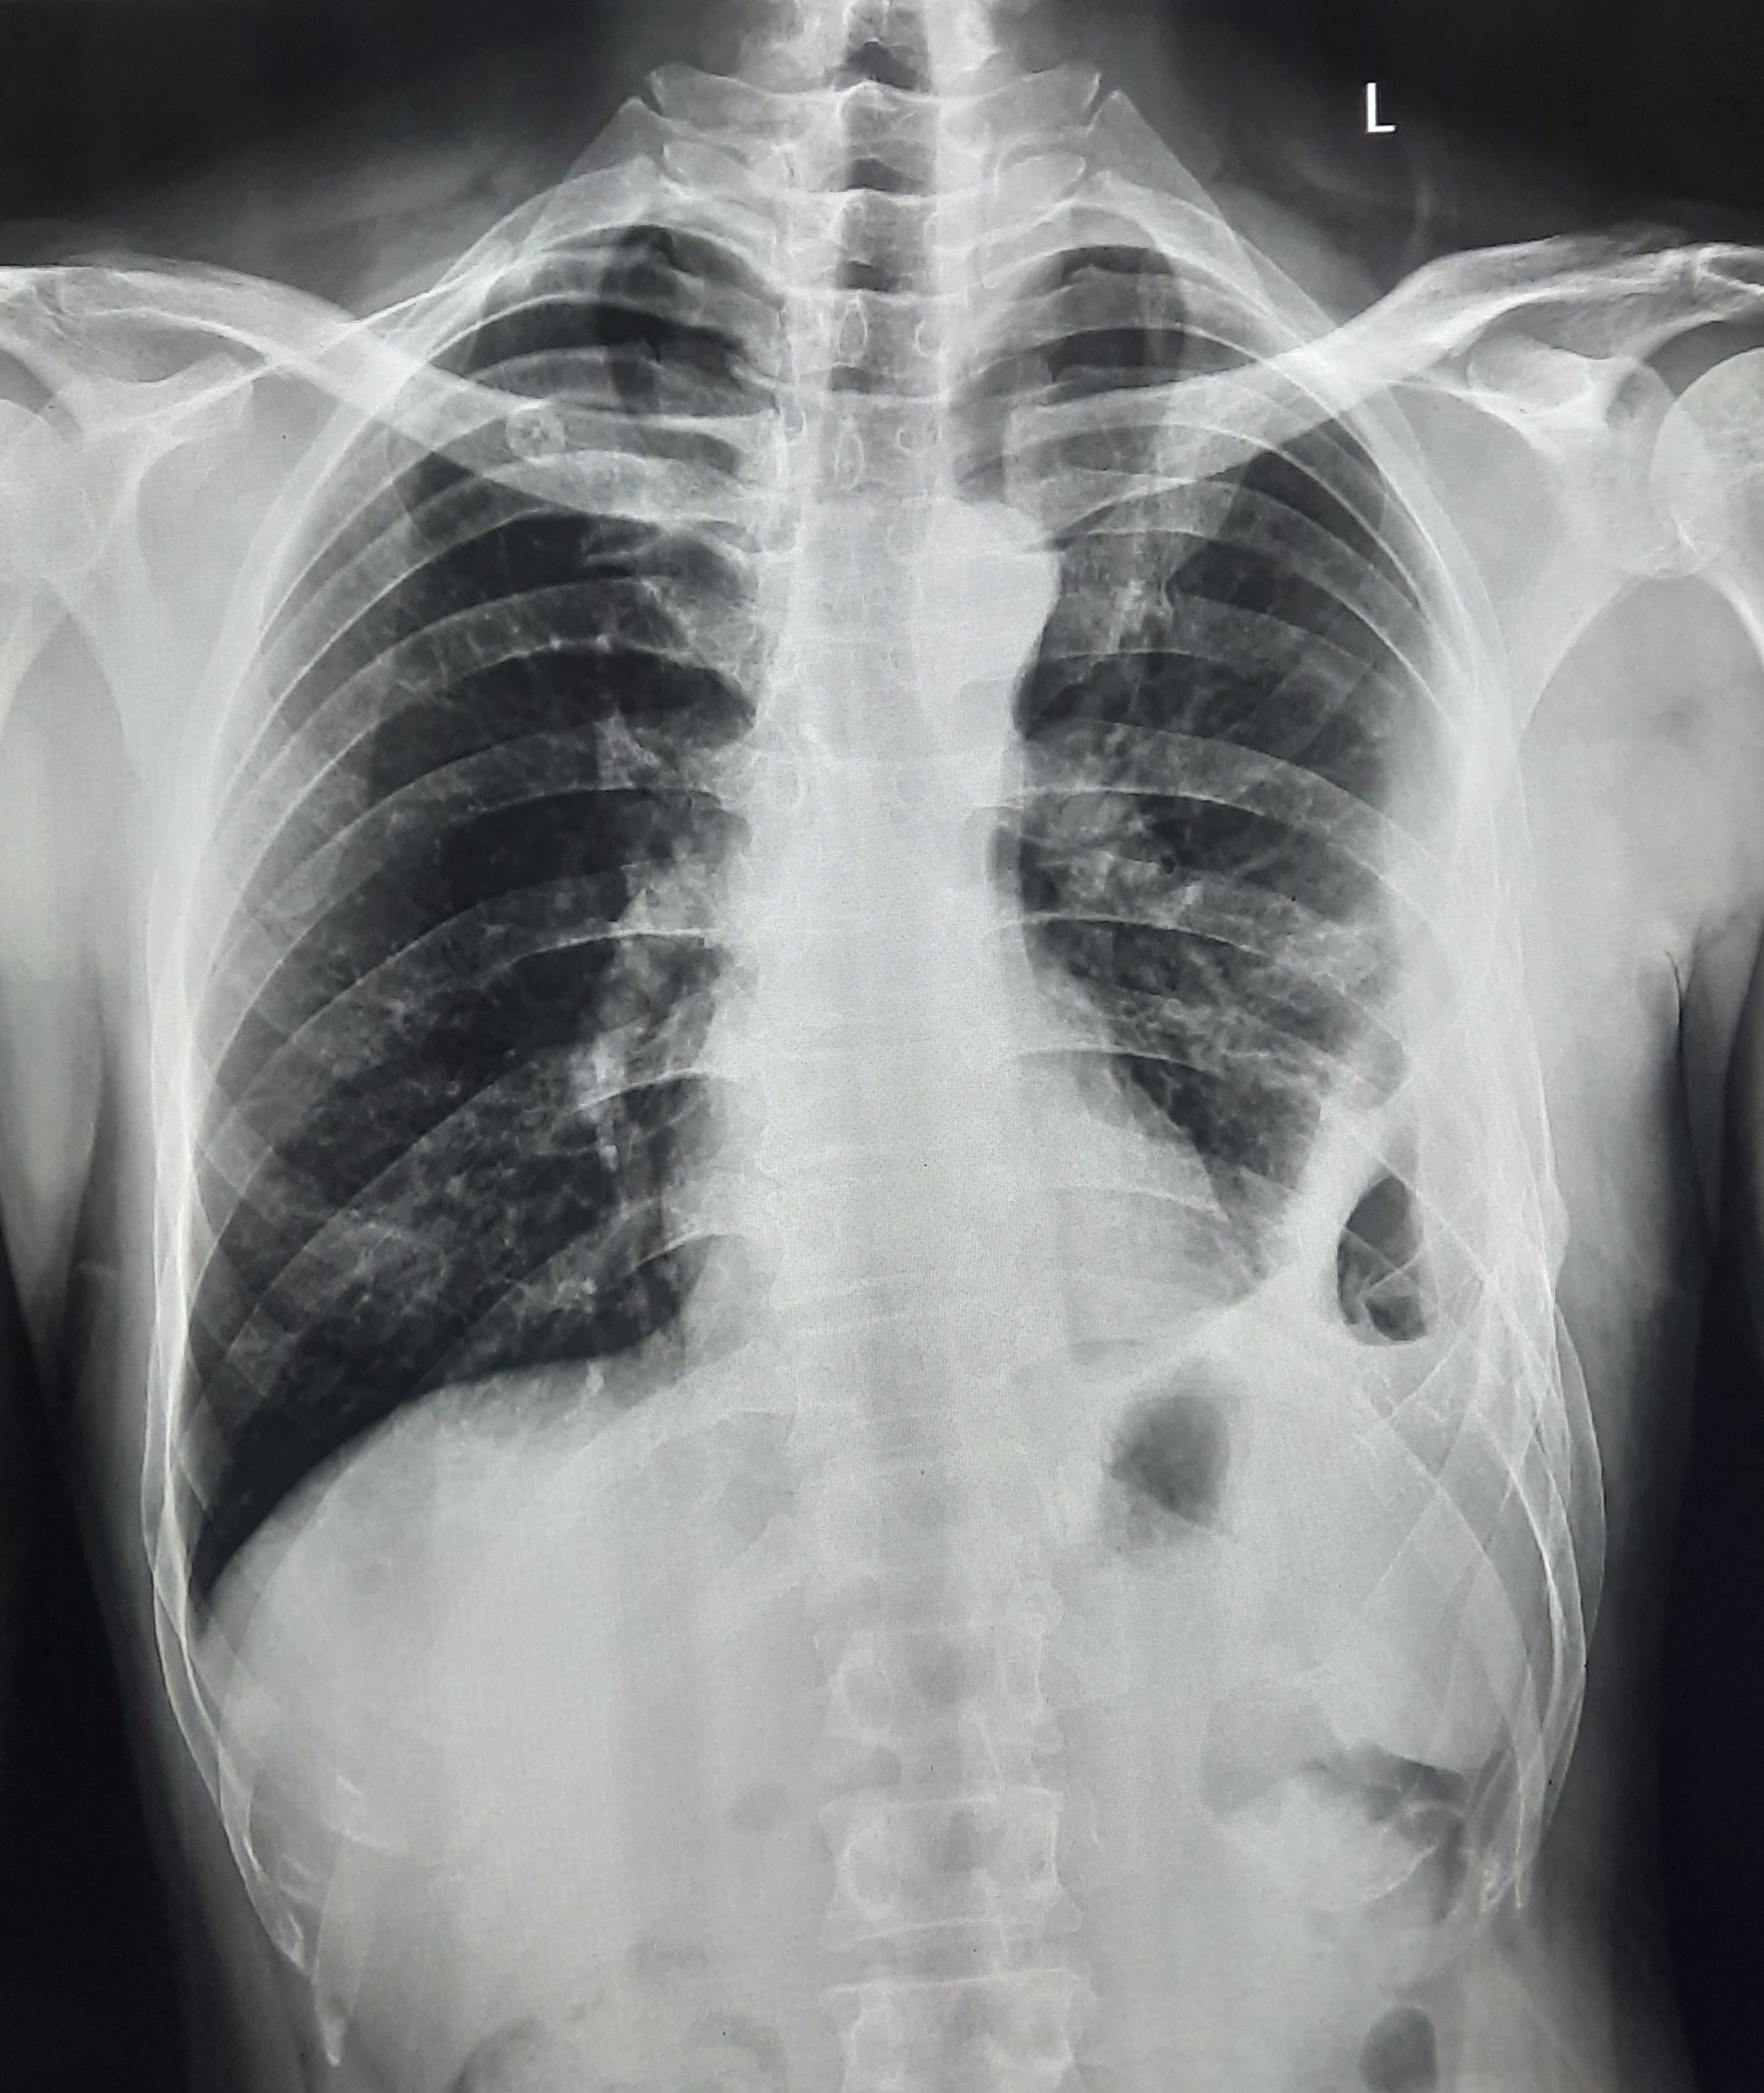

| 150 | IGGMC, Nagpur, Nagpur | P2 | 29-4322 | Anusaya Bajirao | Consent taken on Paper | 68 Yrs. |

Provisional Diag : ?

Final Diag : Post TB Sequel |

Post TB Sequelae | Bilateral Hyper infiltration Present With Bilateral CP Angle Blunting Present With Bilateral Fibrotic Band Present With Prominent Broncho Vascular marking | Abnormality visible on x-ray |